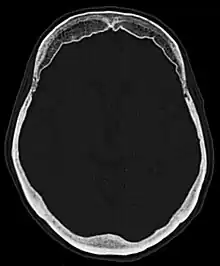

| Hyperostosis frontalis interna in a 74-year-old woman | |

Hyperostosis frontalis interna is a common, benign thickening of the inner side of the frontal bone of the skull. It is found predominantly in women after menopause and is usually asymptomatic. Mostly frequently it is found as an incidental finding discovered during an X-ray or CT scan of the skull.

Hyperostosis frontalis at CT